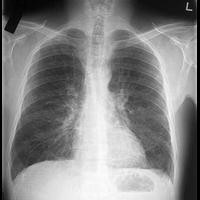

Курение значительно повышает вероятность развития рака лёгких. Хроническая обструктивная болезнь лёгких (ХОБЛ) так же повышает данный риск. Сотрудники центра изучения раковых заболеваний университета Колорадо уточнили ранее неизученный механизм, повышающий риск развития рака лёгких: долговременная нехватка кислорода стимулирует выработку сигналов, которые содействуют росту опухоли.

Результаты исследования работников центра изучения раковых заболеваний университета Колорадо показывают, что опухоли, рост которых стимулируется за счёт ХОБЛ-индуцируемых сигналов, может быть предотвращён.

Не исключено, что для предотвращения роста опухолей лёгких можно использовать ингибиторы ХОБЛ-индуцируемых сигналов, например, ингибиторы VEGFR-2 и EGFR.